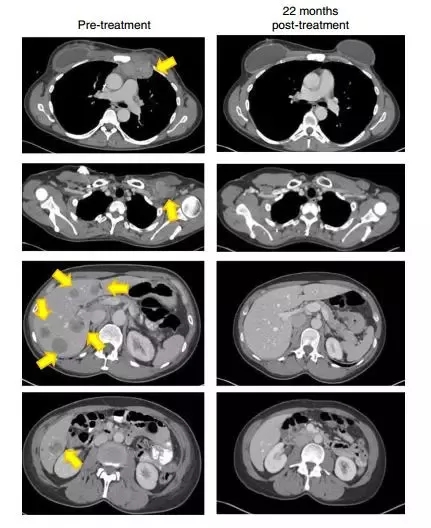

2018年,《自然医学》(Nature Medicine)上发表的一份报告描述了在用对4种突变蛋白(SLC3A2,KIAA0368,CADPS2和CTSB)的TILs治疗的患者中成功治疗化学难治性激素阳性转移性乳腺癌。在报告发表时,反应已经持续进行了22个月以上,并且患者在4年后仍然没有疾病。

22个月后,这名患者的肿瘤(黄色箭头)消失得无影无踪(图片来源:《Nature Medicine》)